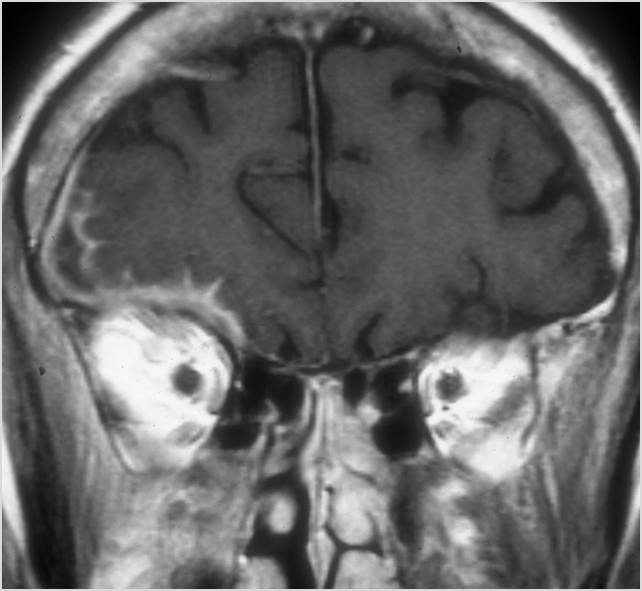

Intracranial

There is a subperiosteal fluid collection or abscess along the boney walls of the anterior or middle cranial fossa. [Yes/No]

There is an epidural fluid collection or abscess along the boney walls of the anterior or middle cranial fossa. [Yes/No]

There is a subdural fluid collection or abscess along the boney walls of the anterior or middle cranial fossa. [Yes/No]

There is a subdural fluid collection or abscess along the falx cerebri or within the tentorium. [Yes/No]

There is evidence of thrombus, thrombophlebitis or other occlusive or inflammatory process of the cortical veins, sphenoparietal sinus or sagittal sinus. [Yes/No]

There is evidence of thrombus, thrombophlebitis or other occlusive or inflammatory process of the cavernous sinus. [Yes/No]

There is brain edema specifically involving the frontal and temporal lobes. [Yes/No]

There is cerebritis specifically involving the frontal and temporal lobes. [Yes/No]

There is brain abscess specifically involving the frontal and temporal lobes. [Yes/No]

There is likely meningitis, meningoencephalitis with complicating hydrocephalus or brain herniation. [Yes/No]